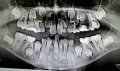

Ребенку 8 месяцев. Повредил десну с помощью игрушки (грыз ее, видимо чесались десна). После повреждения был виден кровоподтек, часть десны была синяя после остановки кровотечения, и торчала верхушка зуба. А на следующий день синяя часть десны оторвалась, и стал виден зуб.

Зарастет ли десна, когда зуб вылезет?

Не волнуйтесь, по мере прорезывания зуба десна восстановится.